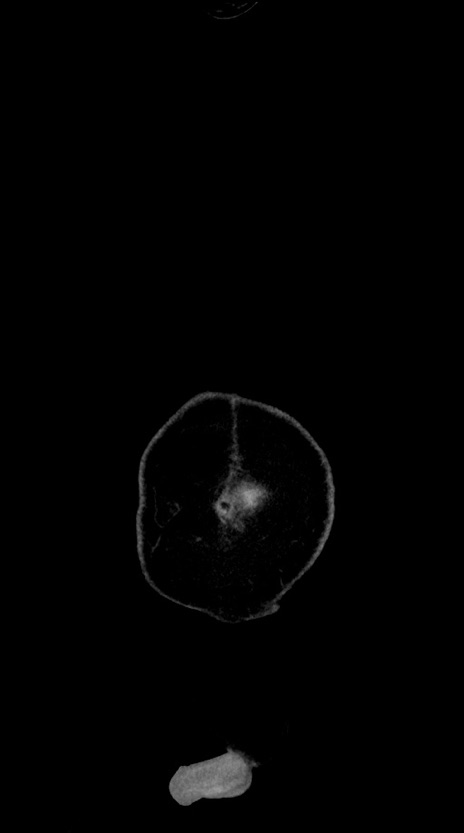

横断像

【症例】60歳代男性

【現病歴】胃癌にて胃全摘後。食思不振が悪化し、夜中に嘔吐することがある。

【既往歴】胃癌、胃全摘、脾摘、胆摘後